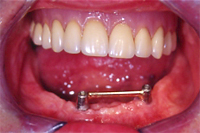

Dieser Fall zeigt eine seit Jahrzehnten gut bewährte Implantatsteglösung im zahnlosen Unterkiefer. Ohne diesen Steg würde die Prothese auf dem profilarmen Unterkiefer beim Sprechen und Essen instabil umherrutschen und das berüchtigte und unwürdige Prothesenklappern verursachen.

Bei diesem 79 Jahre alten, sehr aktiven Senioren haben wir zwei Implantate in der Eckzahnregion im Unterkiefer gesetzt. Zwei Monate später verbanden wir die Implantate starr mit einem Goldsteg (Abb. 11) und setzten die neue Prothese ein.

Die Abb. 12 zeigt die Unterkieferprothese mit Steghülse von innen. Im Mund eingesetzt hält die Prothese stabil und sicher (Abb. 13).